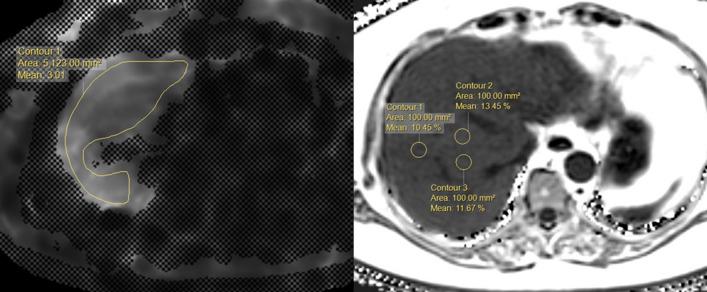

Low cut-off of FIB-4 is a widely used formula to exclude advanced liver fibrosis in primary care centers. However, the range of reported threshold of FIB-4 to rule in advanced fibrosis is too broad across etiologies, and no consensus has been reached. In the present study, we investigated the role of FIB-4 for a reassessment of hepatic fibrosis burden in a referral center. We compared the diagnostic performance of FIB-4 among patients with liver disease of various causes and tried to find an optimal cut-off value for predicting advanced fibrosis. Among 1068 patients, the AUROC of FIB-4 to diagnose advanced fibrosis showed no significant difference among the various etiologies of liver disease, ranging from 0.783 to 0.821. The optimal cut-off value obtained by maximizing Youden's index was 2.68, and the sensitivity, specificity, positive predictive value (PPV), and negative predictive value (NPV) for predicting advanced fibrosis were 70.7%, 79.1%, 43.5%, and 92.2%, respectively. The PPV was low in patients with autoimmune disease (6.67%). When we incorporated the new cut-off of FIB-4 into abdominal ultrasound findings, 81% of unnecessary work-ups would be appropriately avoided. In conclusion, the cut-off value of 2.68 showed an acceptable PPV while maintaining a high NPV to predict advanced fibrosis, most etiology except for autoimmune diseases. This result could assist in establishing an appropriate timing to reassess the hepatic fibrosis burden during monitoring in the referral center.

低截断值的 FIB-4 公式被广泛用于在基层医疗中心排除晚期肝纤维化。然而,由于各病因报道的 FIB-4 诊断晚期纤维化的截断值范围太广,目前尚未达成共识。本研究旨在探讨 FIB-4 在转诊中心重新评估肝纤维化负担中的作用。我们比较了 FIB-4 在不同病因肝病患者中的诊断性能,并试图找到预测晚期纤维化的最佳截断值。在 1068 例患者中,FIB-4 诊断晚期纤维化的 AUROC 在各种病因肝病中无显著差异,范围为 0.783 至 0.821。通过最大化 Youden 指数获得的最佳截断值为 2.68,预测晚期纤维化的敏感性、特异性、阳性预测值 (PPV) 和阴性预测值 (NPV) 分别为 70.7%、79.1%、43.5%和 92.2%。自身免疫性疾病患者的 PPV 较低 (6.67%)。当我们将 FIB-4 的新截断值纳入腹部超声检查结果时,81%的不必要检查可以得到适当避免。总之,该截断值 2.68 预测晚期纤维化的阳性预测值虽然较低,但仍保持较高的阴性预测值,除自身免疫性疾病外,对大多数病因均适用。该结果有助于在转诊中心监测期间确定重新评估肝纤维化负担的适当时机。